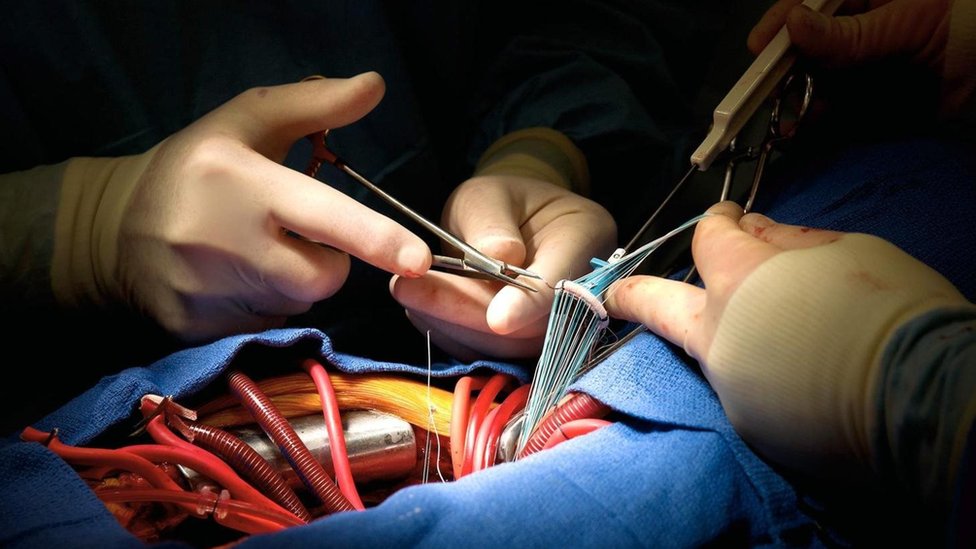

Tras sufrir un infarto, millones de células musculares del corazón se pierden de manera irreversible. Crédito: Getty Images